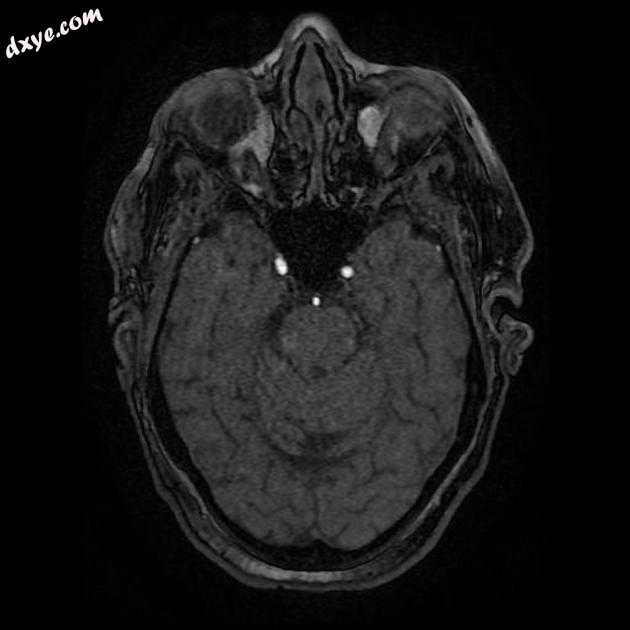

Axial FLAIR

MRI 序列显示左侧大脑中动脉 (MCA) 区域分布中的弥散受限区域,在 FLAIR 序列上不可见。在 GE 序列上没有看到出血性转化。 MRA 3D-TOF 显示左侧大脑中动脉完全闭塞。

早期超急性大脑中动脉 (MCA) 区域梗死的 MRI 特征。